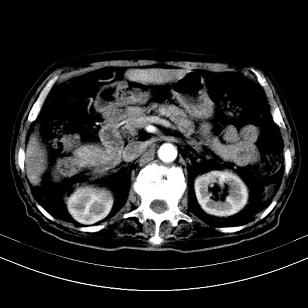

标题: CT19407:肝内还是肝外原发性肿瘤??

男,63岁,高血压病史40余年,

来源-右侧肾上腺。

考虑右侧肾上腺巨大占位;恶性?

肝内多发低密度找;转移瘤?

另:右肾结识,多发小囊肿。

考虑右肝后叶肝癌伴多发肝内转移

考虑右肝后叶肝癌(部分外生)伴肝内多发性转移;右侧肾上腺区恶性肿瘤并肝转移待排。

考虑右侧肾上腺肿瘤并肝内多发转移。右侧肾上腺呈“八”字形,包括内侧枝及外侧枝,内侧枝受压,考虑外侧枝原发肿瘤。”